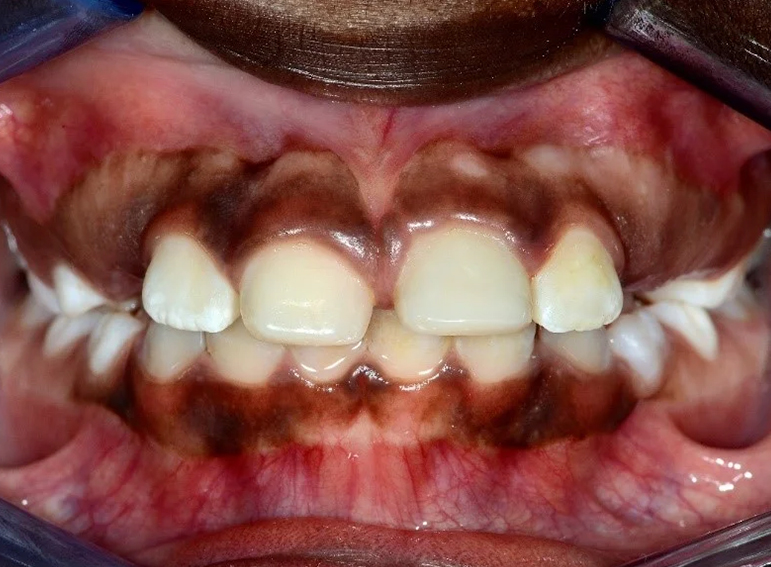

Surgical extrusion, root canal and apexification treatment of UL1 and composite build ups of UR1 and UL1 following dental trauma.